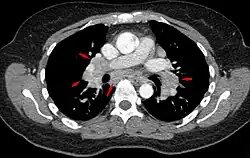

Hilar adenopathy especially on the person's left (AP CXR)

Hilar adenopathy especially on the person's left (transverse CT)